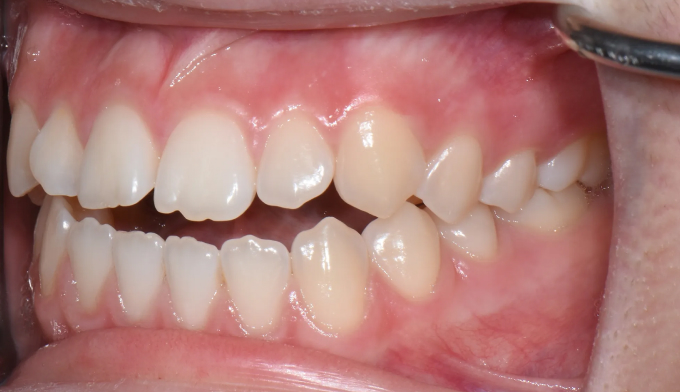

개방교합은 좋지않은 발음을 만들기도 하지만 심미적으로도 좋아보이지 않아서 교정치료를 받으러 많이 오십니다. 치아는 가지런하므로 교정치료가 어렵지 않아 보이지만 개방교합의 치료는 교정용 미니스크류의 식립도 필요하며, 재발도 잘되는 어려운 교정입니다. 교정치료 이후에 재발되지 않게 주기적인 관리 및 연습도 필요합니다.

어금니의 미니스크류의 식립을 통하여 개방교합을 치료하였습니다. 총 치료기간은 13개월입니다.